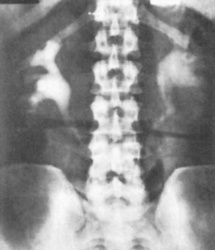

Plain radiography

Plain radiography of the kidney, ureters and bladder (KUB) is a simple, non-invasive test that can be used before specialized imaging. It is used to detect calcification in the kidney, such as renal and urinary tract stones – uric acid stones cannot be detected, but in general 90% of stones are radio-opaque (Figs 8.15 and 8.16). It also shows the size and position of the kidneys (this is unreliable), and any secondary bony deposits (such as can be associated with prostatic cancer).

image

Fig. 8.15 Plain abdominal radiograph showing several calculi in the left kidney (arrows).

(Courtesy of Mr RS Cole.)